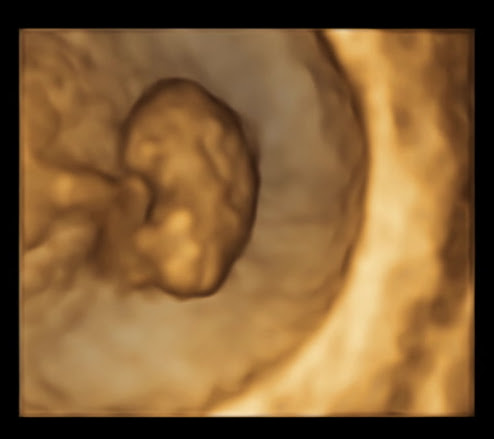

Around the seven to eight-week mark, the magic really starts to unfold. At this point, a transvaginal ultrasound (where a small probe is inserted for a clearer view) can show more defined features, such as the embryo’s shape and a stronger heartbeat.

The baby (still called an embryo at this stage) is only about the size of a blueberry, but you may be able to spot tiny arm and leg buds beginning to form. This is also when the heartbeat becomes more consistent and can be measured for the first time.